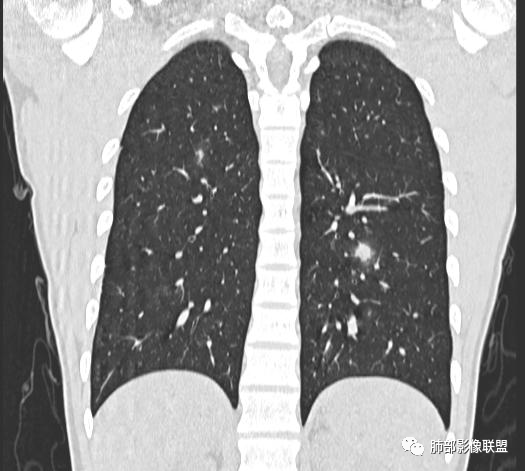

【每日晨读】年轻男性,发热+皮疹+肺内点晕

主  诉:发热、全身皮疹2天。

现病史:患者源于2天前受凉后出现发热,最高体温为38.5℃,且颜面部出现少量皮疹,无鼻塞、流涕、咳嗽、咳痰,未在意而未作特殊处理,次日全身皮疹逐渐增多至全身,伴轻度瘙痒,在当地卫生所给予抗病毒、抗感染治疗(具体用药不详)体温有所下降,但皮疹无明显消退,无腹痛、头痛,食欲无明显减退,为进一步诊治,遂于今日急来我院求治,患者目前精神尚可,体力正常,食欲正常,睡眠正常,体重无明显变化,大便正常,排尿正常。

小强:青年,发热,皮疹;双肺散在结节,周围磨玻璃,点晕征,疱疹病毒感染,鉴别荚膜组织胞浆菌,结核。 大雄:青年,急性起病,发热伴全身皮疹2天,抗病毒治疗体温有下降。双肺随机分布大小不等类圆结节,“点晕征”。考虑水痘-疱疹病毒(VZV)血播询问接触史,查体皮疹分布以及形态基本可诊断。 王开金江津中心医院呼吸科:青年男性,起病急,病程短,以发热,皮疹为首发症状,感染指标以单核细胞升高为主,胸部ct双肺多发结界,周围有晕,点晕表现,随机分布,同意於老师意见,水痘疱疹病毒血流感染累及肺。 王秀仙:双肺多发大小不等结节,周围有晕,边缘模糊,呈点晕征表现。青年,急性起病,发热伴全身皮疹2天,抗病毒治疗体温有下降。考虑疱疹病毒。鉴别荚膜组织胞浆菌。 傅昌瑜:19岁男性,发热、全身皮疹2天,单核细胞增高,双肺多发结节,结节边缘见边界不清磨玻璃影。点晕征+发热、全身皮疹+单核细胞增高——考虑水痘-带状疱疹病毒肺炎。 一切∮随缘:年轻男性,发热,皮疹两天,实验室,CRP,PCT增高,影像:双肺多发散在磨玻璃结节,边界欠清,大小不等,呈点晕征改变,以血管束周围分布为主,局部血管束略增粗,其它无明显改变,考虑:1:病毒性肺炎(水痘疱疹病毒?不知道皮肤有无改变)2:真菌(组织胞浆菌,血管侵袭性肺曲霉)3:GPA4:寄生虫(实验室没有看到嗜酸细胞增高) 赵山河:双肺散在结节,周围有晕,边缘模糊,呈点晕征表现。青年,急性起病,发热伴全身皮疹2天,抗病毒治疗体温有下降。考虑水痘—疱疹病毒感染。洪桥爱:青年男性,发热、皮疹2天,伴瘙痒,皮疹于面部首发,之后进展至全身,虽然没有对皮疹进行描述,但是从出疹时间及皮疹进展情况,伴瘙痒,应该就是个水痘患者;CT提示双肺随机分布结节影,部分结节伴有边界不清晕征,考虑水痘血播肺。 刘强:年轻男性,急性起病,皮疹,发热,抗感染治疗体温下降,说明有效。影像表现为散在点晕征,感染类疾病谱(疱疹病毒,真菌,结核),结合年龄,皮肤皮疹,考虑水痘-疱疹病毒性肺炎。 小兜:男性,19岁,发热皮疹两天,颜面部至全身,CRP,降钙素及单核增高。CT示双肺散在小结节,周围伴磨玻璃影,点晕征,考虑为水痘-带状疱疹病毒(varicella-zoster virus,VZV)肺炎 必有路:青年,皮疹+发热+“点晕征”→水痘-疱疹病毒(VZV) 许慧良:青年男性患者,发热、皮疹2天,体温最高38.5℃,第3天皮疹扩展至全身,伴瘙痒,胸部CT:双肺多发随机分布的小结节,结节周边见边界模糊的晕征,考虑水痘病毒感染流心明智:男,19,急性起病,发热伴全身皮疹2天。出疹顺序头→全身,抗病毒有效。胸部CT:两肺多发大小不等类圆形实性小结节影,随机分布,结节周围环绕GGO,边界模糊,呈点晕征。出疹特点是关键,未提示。考虑:血播病毒性肺炎,水痘-疱疹病毒?麻疹?鉴别荚膜组织胞浆菌、TB、血管炎、寄生虫等。 浪迹天涯:病灶多为5-10mm大小结节,结节周围可见磨玻璃样的晕环,常多发,可分布于肺内任何区域,考虑水痘—带状疱疹病肺炎如果短时间内有新的一个区域浸润,更加能说明,